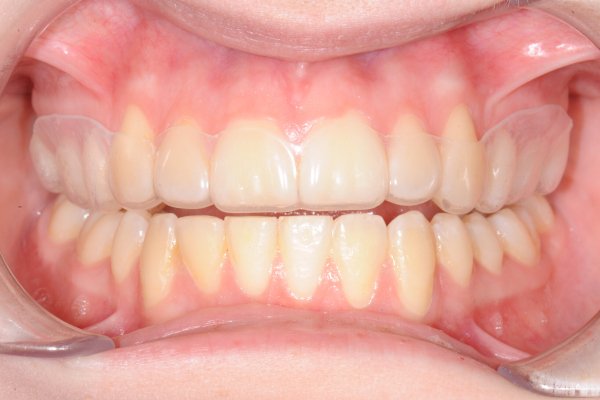

Remember that your treatment is not complete once the braces have been removed. In order to keep your teeth in their new position, they need to be stabilised. Stabilisation is done by either using an essix splint at night or by using a glued-on metal wire.

We call this "retention". Retention is important because the teeth want to return to their original position. If you end retention too early, your bite may look like you never had braces after a few years. Therefore, you should follow this advice.

Essix splint

The Essix splint is removable. Unless otherwise instructed, the Essix splint is used every night for the first year. Thereafter, the use is reduced by using the Essix splint every other night for six months, followed by further reduction. Two years after the braces have been removed, you use the Essix splint 1-2 nights a week. If you want your teeth to remain in the position they are in after treatment, you need to use the essix splint 1-2 nights a week as long-term retention.